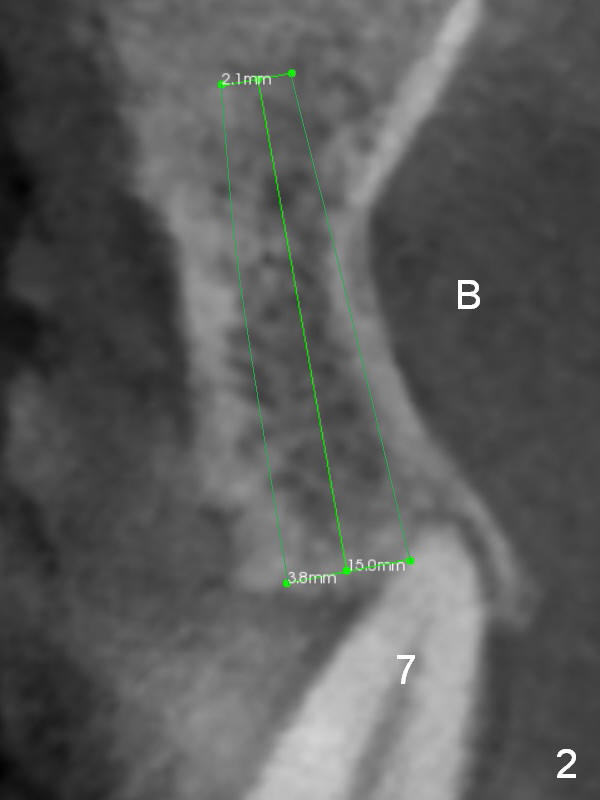

Because of back pain, the 45-year-old man requests less implants (#7 and 13) in the second surgery than the previous one (#9-11, 15).

After extraction of the labioincisally displaced #7 (Fig.1, Metronidazole), place either 1 or 2- (Fig.2) piece implant. For the latter (bone density 200-800 units), prepare cemented or angled abutments with 5 mm cuff. Use a crown form for provisional (single unit).